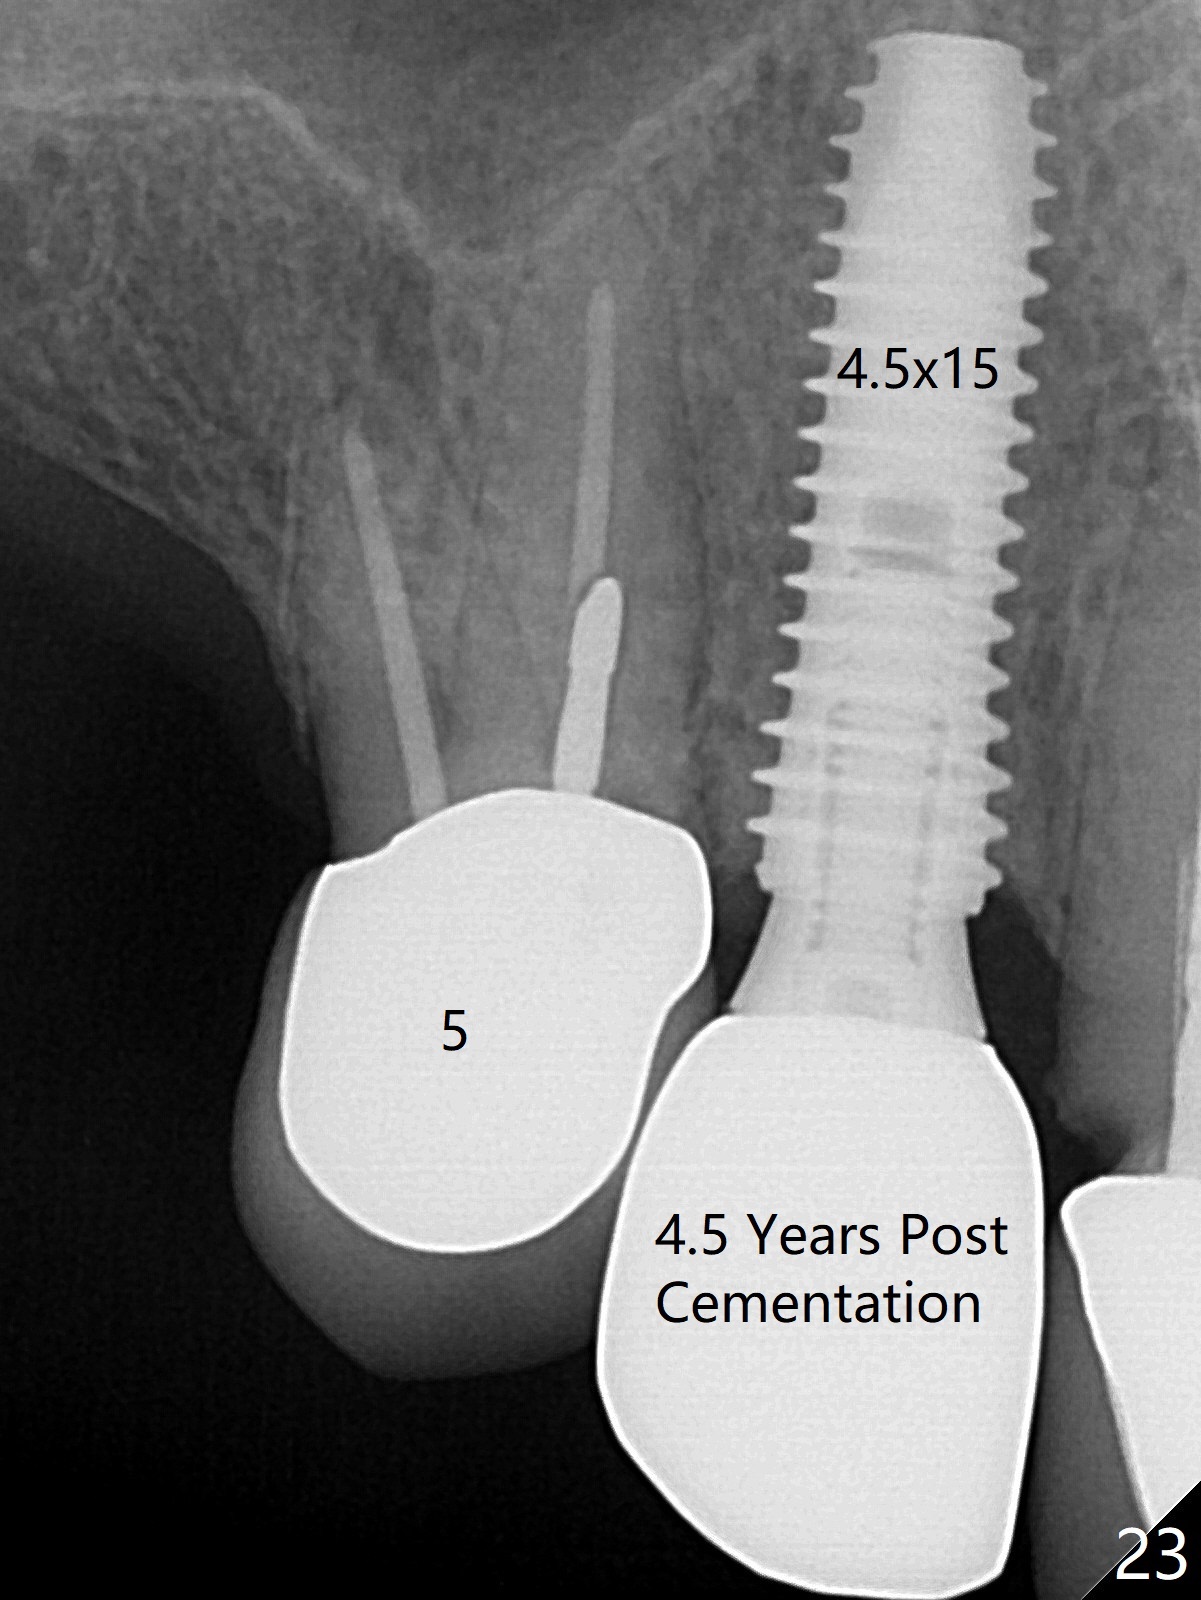

Six months post cementation, the tooth #9 becomes symptomatic. Is it possible that the implant at #10 is too close to the root of #9? It is asymptomatic after pulpotomy, but the tooth fractures equi/supragingivally. Two PAs taken while RCT show osteointegration at #10-12 (Fig.18,19). While the bone density increases at #10 regular implant, there is minimal bone loss around the 1-piece implants 13 months post cementation (18 months postop, Fig.20,21). The gingiva remains healthy 19 months post cementation (Fig.22). 76岁病人突然打电话说一个植牙牙冠松动,其实9号牙(自然牙)折裂,6,10-13号牙植牙好像没有骨质吸收(图二十三至二十五),10-13牙位牙龈健康(图二十六,行使功能五年)。9号牙牙冠重新粘固后,显示前牙深覆合,深覆盖(图二十七,二十八)。如果再次脱落需要植牙,选择一段式有助于植入和修复,因为植体和基台直径小。两段式植牙相对基台直径至少4,或者4.5毫米,前牙修复显得笨重。由于9,10牙根和植体接近,9号牙植体需要偏小而长,3x14或者15毫米(图二十九)。